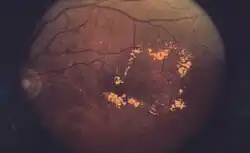

El diagnóstico debe realizarlo el oftalmólogo, que puede distinguir el engrosamiento de la mácula mediante técnicas especializadas; también puede sospecharse mediante la exploración con oftalmoscopio en la que se aprecia una zona de exudados amarillentos que rodean a la mácula, asemejándose a una corona (ver imagen).